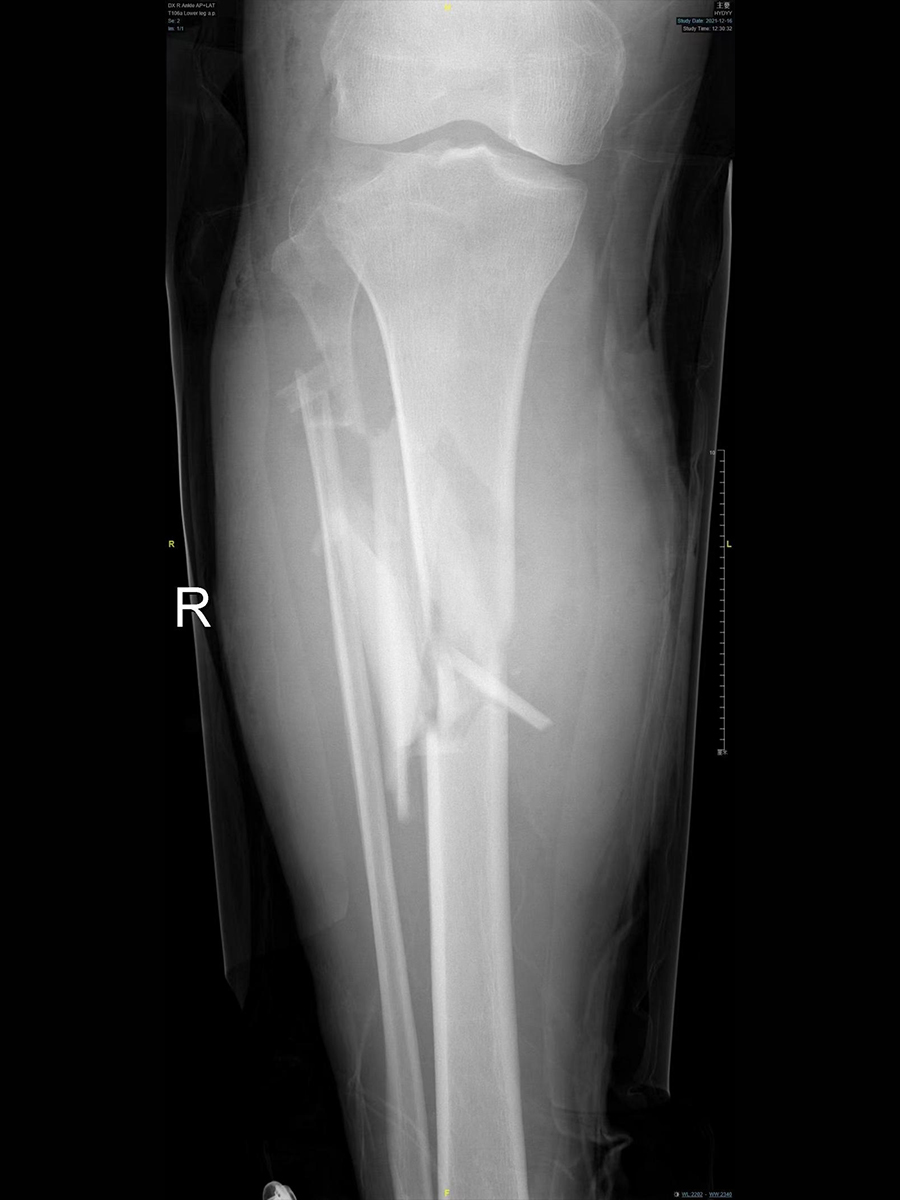

患者因为车祸导致的小腿开放性骨折,据患者描述:车祸发生时原本站在车尾,却被追尾的后车夹在两辆车之间。受伤后小腿出现肿胀、流血、畸形,由120急救车送到急诊室。刚到院时,小腿被夹板固定,可以看到被血液浸湿的绷带。拆除敷料进行初步查体:小腿存在多处伤口,一处较大的伤口长约15cm,内部填满了泥土,还能看见外露的骨折端。X光片显示胫腓骨多处骨折。患者最终确诊为开放性骨折。

患者入院5个小时后接受了手术治疗,第1次手术后,骨折在外固定架的辅助下恢复了正常力线,小腿的创口于术后16天左右愈合。出院后3个月,患者的血常规、血沉、C反应蛋白恢复正常,再次住院行第2次手术,术后切口顺利愈合,没有感染的表现。又3个月后,复查X线,创口愈合,骨折愈合良好。